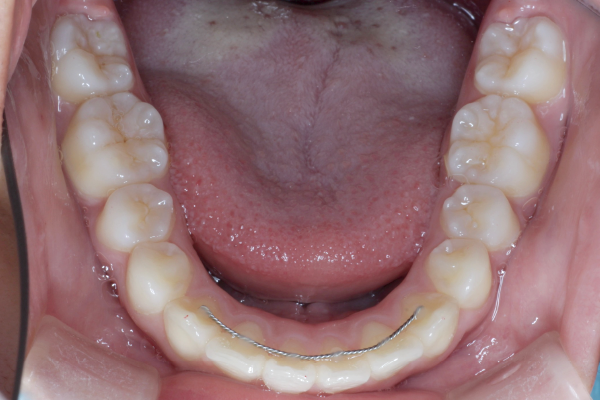

約2年間にわたる矯正治療は決して簡単なものではありませんでしたが、最後までしっかり通院していただき、良好な歯列を獲得することができました。今後は後戻りのチェックとともに、定期的なメンテナンスと虫歯予防を継続していくことが大切です。

【矯正治療開始11ヶ月】

11ヶ月経ち歯のガタガタが改善し、歯並びが綺麗になってきています。